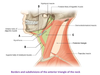

What are the 2 triangles of the neck?

Anterior and posterior triangles

What is A?

Stylohyoid muscle

What is B?

Mandible